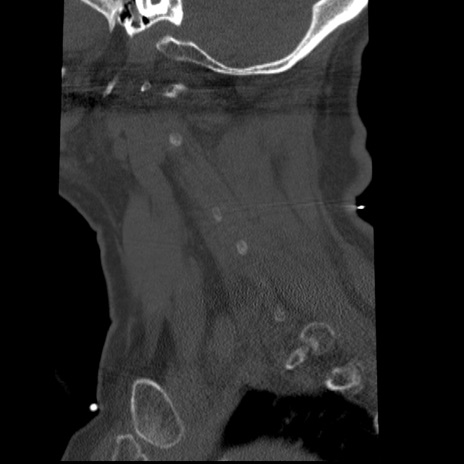

症例50 頚椎CT(矢状断像)

頚椎CT